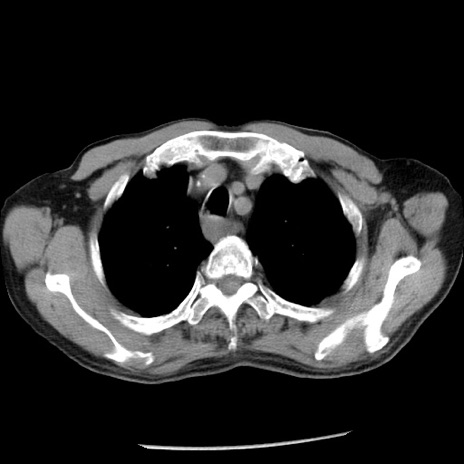

症例26(横断像)

【症例】80歳代男性

【主訴】嘔吐

【現病歴】昨晩2回嘔吐あり、今朝になっても嘔吐あり。来院。

【既往歴】胃潰瘍

【身体所見】意識清明、BT 37.6℃、BP 166/95mmHg、HR 100bpm、SpO2 97%、腹部:平坦・軟、腸蠕動音聴取良好、圧痛なし。

【データ】WBC 21900、CRP 1.46